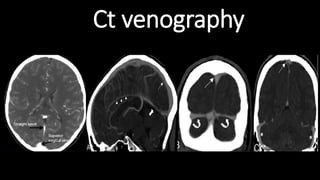

Ct venography

The Venous Drainageof the Central Nervous System • The dural venous sinuses lie between the periosteal and meningeal layers of the dura mater. They are best thought of as collecting pools of blood, which drain the brain. • Unlike most veins of the body, the dural venous sinuses do not have valves. • All the dural venous sinuses ultimately drain into the internal jugular vein.

• 52.

• The straight,superior, and inferior sagittal sinuses are found in the falx cerebri . They converge at the confluence of sinuses (overlying the internal occipital protuberance). • The straight sinus is a continuation of the great cerebral vein and the inferior sagittal sinus. • From the confluence, the transverse sinus continues bi-laterally and curves into the sigmoid sinus to meet the opening of the internal jugular vein. • The cavernous sinus drains the ophthalmic veins and can be found on either side of the sella turcica. From here, the blood returns to the internal jugular vein via the superior or inferior petrosal sinuses. The Venous SINUSES